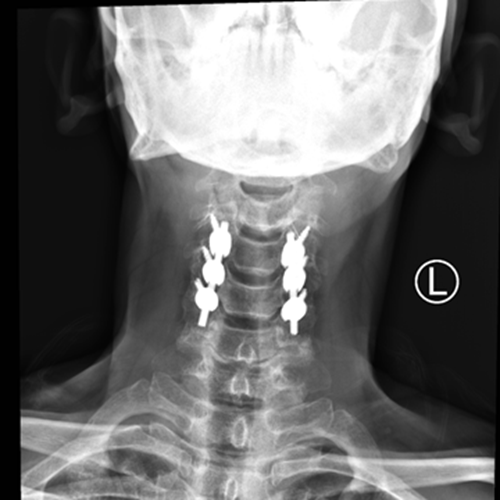

近日,湘雅常德医院骨科收治了一名“颈部脊髓损伤伴四肢不全瘫”的外伤患者,并顺利完成手术,使患者瘫痪症状得以恢复。    2018年6月30日下午,家住桃源县63岁的曾大叔在工地...